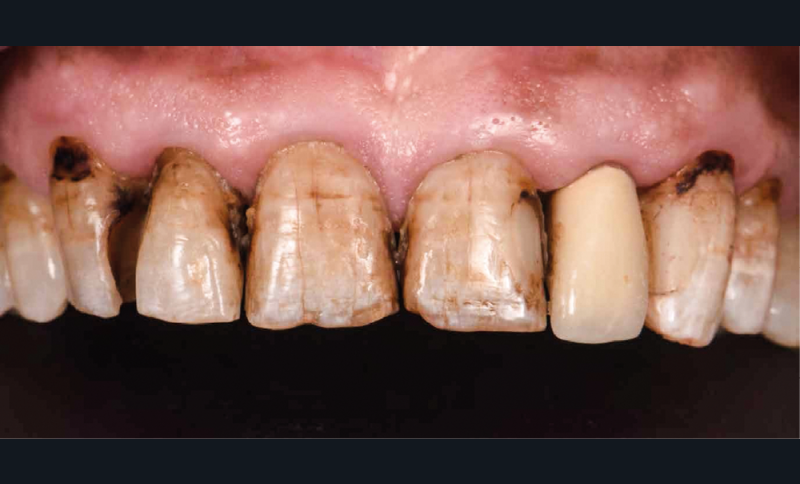

Un patient, âgé de 62 ans, nous consulte pour la réhabilitation de son sourire qu’il trouve disgracieux. Il est gêné par la longueur et l’aspect opaque de son incisive latérale supérieure gauche et, de manière générale, par la couleur et les fêlures présentes sur ses dents antérieures maxillaires.

On note la présence d’anciennes restaurations composites, de lésions carieuses actives et de pertes de substances amélo-dentinaires (fig. 1).